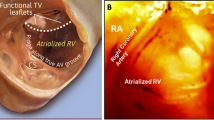

Right free wall was arbitrarily divided into four regions depending on the orientation of the loop and the tip of the ablation catheter as seen with the ICE (Fig. 1): 3 patients (37%) had anterior location of the accessory pathway with the loop of the ablation catheter oriented vertically and the tip being lateral from the location of the His bundle (Fig. 2); 1 patient (12%) had an anterolateral location of the accessory pathway with the loop and the tip of the ablation catheter oriented oblique toward the upper right part of the tricuspid annulus (Fig. 3); 3 patients (37%) had a lateral location of the accessory pathway with the loop and the tip being oriented horizontally (Fig. 4); 1 patient (12%) had a postero-lateral location of the accessory pathway with the loop and the tip of the ablation catheter oriented oblique toward the lower right part of the tricuspid annulus (Fig. 5).

Intra-cardiac echocardiography (ICE) image taken during mapping and ablation of the an-terior right free wall accessory pathway (AP). The 10 Fr (French scale) ICE probe was in-serted into the right atrium via the femoral vein. The ablation catheter was inserted into the right ventricle via a steerable long sheath and the described “loop” manoeuvre was used. White lines mark the presumed location of the steerable long sheath, yellow lines mark the course of the ablation catheter loop. The tip of the ablation catheter is marked with a solid white arrow, the tricuspid valve is marked with solid white arrowheads. RA right atrium, RV right ventricle, Ao aorta.